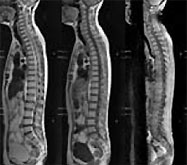

MRI(Philips Gyroscan Intera / Achieva)

MRIは放射線を使わず、強い磁石と電波を使って写真を撮影する検査です。被ばくの心配がなく、様々な角度から体の断面を詳しく観察できます。